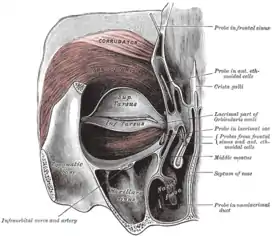

Left orbicularis oculi, seen from behind. (Infraorbital labeled at lower left.) | |